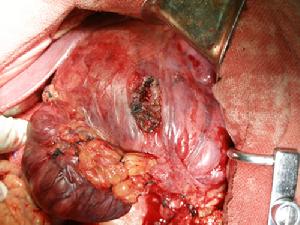

治療腹膜後腫瘤術後復發多為原位復發,很少遠處轉移,為再次手術提供了條件。Karakousis等報導33例復發性腹膜後軟組織肉瘤,29例獲得了再次完全切除其5年生存率為57%中國也有學者報導33例復發性腹膜後肉瘤再次完整切除17例,5年生存率為42%。腹膜後復發性腫瘤再手術切除率和手術效果都比較好有的病例需多次手術才能達到治癒目的。如再次手術時腫瘤已侵犯鄰近臟器,應在不影響功能的情況下聯合臟器切除;對不能完全切除的復發腫瘤亦應最大限度地部分切除,達到減瘤的目的,這不僅可以減輕腫瘤對臟器的壓迫,也可以為術後其他輔助治療創造條件。

大血管損傷和術中大出血是復發性腫瘤再手術經常遇到的棘手問題。如腫瘤來源於大血管或浸潤大血管時,若強行剝離會損傷血管而發生大出血若不切除血管周圍的腫瘤組織,則可導致術後的腫瘤再發所以,在腹膜後腫瘤再手術時,更應考慮到血管的重建問題。腫瘤侵及下腔靜脈在腎靜脈以下切斷或結紮後,血液可經腰靜脈叢等側支回流,不必作血管移植。為了防止術後下肢水腫,在腔靜脈切除後最好能行人造血管移植。腹主動脈段切除後要移植人造血管,腹主動脈的切除長度不應超過3對腰動脈,否則可因脊髓缺血而引起截癱。髂血管切除3cm以上時需移植血管3cm以下時經游離後可行對端吻合。切除盆底腹膜後腫瘤時為了減少出血可先行兩側髂內動脈結紮,並不會影響盆腔臟器的血供。